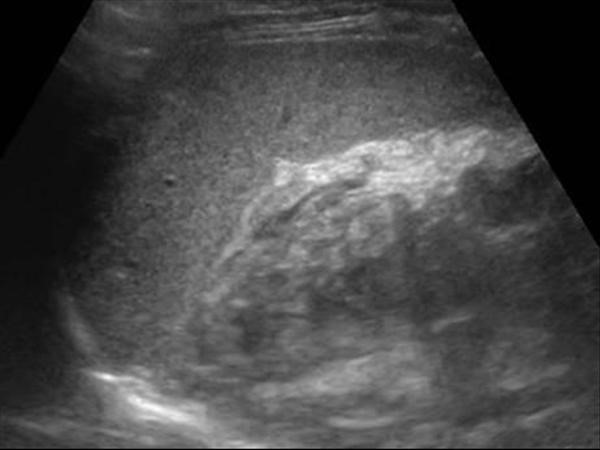

На представленном изображении поджелудочная железа выглядит без патологий. Наблюдается нормальная эхогенность и однородная структура.